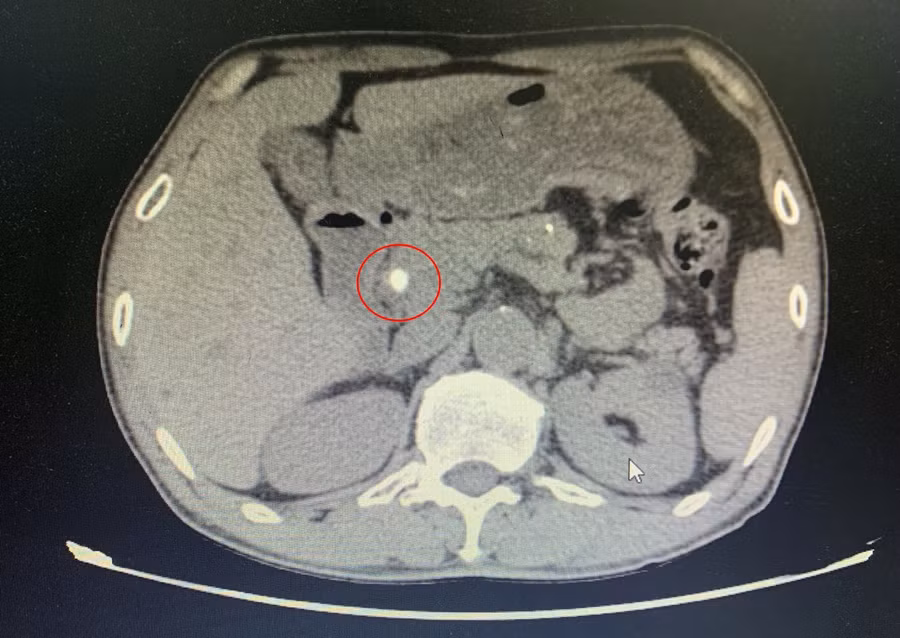

Hình chụp cắt lớp vi tính sỏi ống mật chủ của bệnh nhân T. Ảnh: BVCC

Gần đây, bệnh nhân ở nhà mệt mỏi, ăn uống kém, đau âm ỉ vùng thượng vị và hạ sườn phải, vàng da, củng mạc vàng nên đến viện kiểm tra. Qua thăm khám và chụp cắt lớp vi tính, các bác sĩ thấy đường mật trong ngoài gan giãn nhiều, ống mật chủ có sỏi kích thước 10mm.

Bệnh nhân được chẩn đoán nhiễm trùng đường mật do sỏi ống mật chủ. Hội chẩn đánh giá bệnh nhân bị viêm túi mật mạn tính, ống mật chủ có sỏi to chỉ định phẫu thuật nội soi cắt túi mật và lấy sỏi ống mật chủ.